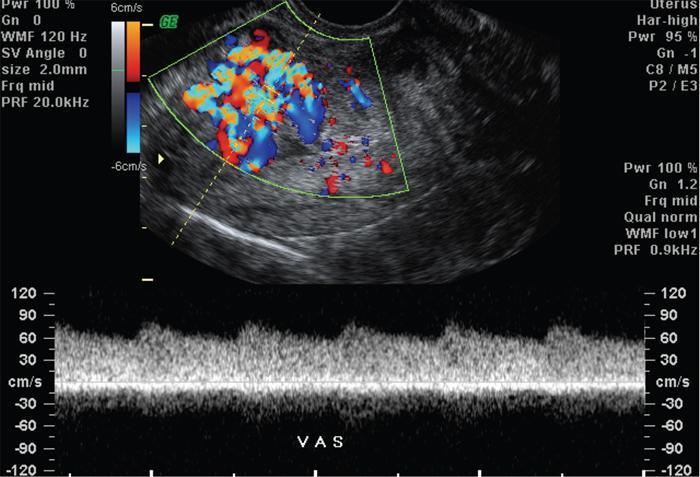

John De Lindsay, Sumathy, Vasumathy, Usha nandhini Ganeshan, N. Sundari ENDOMETRITIS Endometritis is defined as the inflammation of the uterine endometrial layer. Endometritis is frequently observed in the pregnant and postpartum population. Pelvic inflammatory disease (PID) and invasive gynaecological procedures are the most common causes of acute endometritis in nonobstetric population. Endometritis is the most complex asymptomatic and often presents with subclinical form of PID. Ultrasound may reveal minimal particulate endometrial fluid with mildly thickened endometrium showing increased vascularity. Computed tomography (CT) findings include a diffusely bulky uterus due by inflammation, mild fluid distension of endometrial cavity and striking endometrial enhancement in comparison to the adjacent myometrium due to mucosal hyperaemia. ‘Indistinct uterine border’ sign is observed in patients with endometritis, which is defined as the loss of distinction between the uterus and the adnexa. Since it is also observed in the cases of endometriosis or malignancy, it is a nonspecific sign. The age of the patient, clinical presentation, and the biopsy of endometrium helps in differentiating endometritis from other pathologies. UTERINE ARTERIOVENOUS MALFORMATION Uterine arteriovenous malformation (UAVM) is an abnormal connection between the arteries and the veins of the uterine myometrium without an intervening capillary bed. They were first reported by Dubreil and Loubat in 1926. They can be congenital or acquired. Even though UAVMs have varied presentation, uterine bleeding is the most common one. They often follow a pregnancy event. Episodic or occasionally torrential vaginal bleeding can occur. Congestive heart failure secondary to vascular steal can be a rare presentation due to a large UAVM. UAVM is most commonly an acquired condition. Pregnancy has a significant role in their pathogenesis. It is most commonly observed in reproductive age group. UAVMs are frequently observed in the postpartum period, few months after spontaneous miscarriage, surgical evacuation of uterus for miscarriage or medical termination of pregnancy. Infection, inflammation, retained products of conception (RPOC), gestational trophoblastic disease (GTD), gynaecologic malignancies, pelvic trauma and exposure to diethylstilboestrol can also lead to UAVMs. Few cases are also reported in young adolescent and postmenopausal females. UAVMs rarely are congenital and may be also associated with AVMs in other locations. Congenital AVMs Congenital AVMs have a central nidus with multiple feeding arteries and draining veins. In this condition, there is extension of the lesion beyond that uterus and multiple pelvic vessels other than uterine vessels draining into them. That cause of congenital AVMs are thought to be due to failure of embryological differentiation. With the progression of pregnancy, these vessels have the propensity to invade surrounding structures. Iatrogenic Acquired AVMs When the venous sinuses are incorporated into the scars of myometrium after the necrosis of chorionic villi, acquired malformations may arise. In contradiction to congenital AVMs, acquired AVMs multiple fistulous communication between the intramural arteries and the venous plexus. These AVMs may have either dual blood supply or a single supply from the uterine arteries and presents without nidus. Vaginal bleeding caused by pregnancy-related causes must be differentiated from UAVMs. Surgery/evacuation is the appropriate management for the former and the same is contraindicated in the UAVMs and hence an accurate definitive diagnosis is important. Grey-scale ultrasound findings are nonspecific and they are subtle heterogeneity of myometrium with multiple tubular or ‘spongy’ anechoic or hypoechoic areas. In spite of varied presentations such as an intramural uterine, endometrial or cervical mass-like lesions or prominent parametrial vessels, it has minimal mass effect. On colour Doppler, within the myometrium, a region of increased vascularity and most commonly with aliasing is seen. A group of vessels traversing the myometrium running perpendicular to and into the endometrium, from the arcuate vessels, can be seen. It is not specific, as they are also observed in RPOC, GTD, placental polyp and vascular endometrial neoplasm. In pulsed Doppler, multidirectional turbulent flow with intense vascularity can be seen with high peak velocity (mean peak systolic velocity [PSV] = 136 cm/s) and low resistance (mean resistance index = 0.3) flow. The arteries have low pulsatility while the draining veins are pulsatile and show high velocity flow. Magnetic resonance imaging (MRI) offers noninvasive confirmation of the diagnosis of UAVM. T1-weighted and T2-weighted images show multiple serpentine signal voids along the uterine wall, endometrial cavity and parametrium. Contrast-enhanced MR angiography shows intensely enhancing complex serpentine abnormal vessels with early venous return. Catheter angiography can be reserved only for women who require embolization of the AVM. The consent for both diagnostic angiography and therapeutic embolization should be obtained simultaneously to avoid repeat therapeutic procedures. Management of UAVM depends on: UAVM can be treated with medical therapy with hormones, uterine artery embolization or with definitive hysterectomy. Once the diagnosis of a UAVM is confirmed, the treatment option depends on the clinical condition of the patient. The size of the AVM bears no correlation to the need for embolization. Timmerman et al. found that AVMs having PSV of at or above 0.83 m/s, most often requires embolization. Also, the vascular malformation with PSV value below 0.39 m/s does not require embolization. Placental bed subinvolution, enhanced myometrial vascularity (EMV), molar pregnancy or RPOC are the other causes of uterine mass vascular malformations which usually has a mean PSV of 0.52 m/s and does not require embolization. Transcatheter targeted uterine artery embolization is indicated in selected cases, if bleeding persists to a degree that blood transfusions are required to maintain haemodynamic stability or multiple repeated acute hospitalizations. This is preferred over surgical management owing to its immediate minimally invasive and fertility sparing benefits. Gelfoam had been suggested earlier as the material of choice for embolization. Various other embolic materials like polyvinyl alcohol, Histoacryl glue, stainless steel coils, detachable balloons, and haemostatic gelatin are also used nowadays. Normal intrauterine pregnancies after embolization have been reported, proving that an adequate collateral blood supply can develop to support a full-term pregnancy. Gestational Trophoblastic Disease RPOC: Presence of endometrial pathology rather than myometrial origin. FIBROIDS Leiomyomas, also known as fibroids or myomas, are the most common gynaecologic neoplasms, occurring in 20%–30% of women of reproductive age. Symptomatic uterine fibroid accounts for about 30% of hysterectomies performed for women older than 18 years of age and 41% of hysterectomies performed for women from 44 to 64 years of age. Leiomyomas are the benign neoplasms made up of whorled fascicles of smooth muscle and fibrous connective attached to the uterine muscular wall. Even in the absence of true capsule, leiomyomas are well circumscribed and contains a pseudocapsule. Its size is variable, ranging from tiny microscopic to large tumours filling the abdomen. Most commonly, the uterine leiomyomas are seen in the myometrium of uterine corpus. However, it is also seen in the cervix (<5% of cases). On the basis of the location, uterine fibroids are classified as submucosal, intramural or subserosal. This classification is of clinical significance because the symptoms and treatment vary among these subtypes of leiomyomas. Submucosal myomas are further subclassified as 0, I and II depending on the percentage within the endometrial cavity. The first two categories can be removed hysteroscopically (Table 11.15.3.1). Pedunculated leiomyomas are attached to the uterus by a stalk and may be either intracavitary or exophytic (narrower than 50% of diameter of myoma). Rarely, a submucosal fibroid may grow pedunculated and extends into the cervical canal or vaginal canal and its prevalence is about 2.5%. Pedunculated subserosal leiomyomas may undergo torsion, resulting in infarction accompanied by pain. Lateral growth into broad ligament leads to intraligamentous leiomyoma (Table 11.15.3.1). Rarely, a pedunculated leiomyoma may become detached from the uterus (parasitic leiomyoma). Depending on the location, size and number of uterine fibroids, it has varied presentation. Symptoms caused by leiomyomas are classified into three different categories such as abnormal uterine bleeding, pelvic pressure and pain and reproductive dysfunction. Submucosal leiomyomas and intramural leiomyomas are often associated with menorrhagia (Table 11.15.3.1). Because of leiomyoma, uterus may be irregularly shaped and causes symptoms based on their locations. Anterior leiomyomas cause urinary symptoms, whereas the posterior leiomyomas cause constipation. Ureter may be compressed by broad ligament leiomyomas and presents as hydroureter or hydronephrosis. In case of degeneration or torsion of a pedunculated leiomyoma, acute pain may be the presentation. Leiomyomas are an infrequent primary cause of infertility. Malpresentation, pregnancy failures and dystocia are reported. Ultrasound is the first-line imaging modality because it is a cost-effective portable real-time examination that provides good anatomic detail. Leiomyomas appear as a well-defined round or oval hypoechoic solid mass. It is mostly associated with posterior shadowing possibly due to calcifications or interface of the margins of the leiomyoma with the normal myometrium. Degeneration or lipoleiomyoma can be suggested when there is internal echo-poor or hyperechoic foci, respectively. The presence of hypervascularity in a large solitary uterine mass can identify suspicious masses, such as a leiomyosarcoma (LMS). Another study found that there is an increased detection rate of uterine sarcomas while using a cut-off value of 41 cm/s. In the assessment of a uterus enlarged with multiple leiomyomas, ultrasound has FOV limitations. Likewise, it has limited role in the assessment of retroverted uteri, pedunculated subserosal myomas and concomitant adnexal processes. Little has been reported regarding sonographic changes after MR HIFU and uterine fibroid embolization (UFE). Differential diagnosis has been discussed in Table 11.15.3.2. Hyperechoic unlike a myomatous polyp which appears hypoechoic Heterogeneous endometrium with little mass effect Enlarged uterus and a deformed contour are the most common computed tomography (CT) findings. Even though CT is the primary modality for the staging of cancers, it has limitation of reduced contrast resolution for the assessment of focal myometrial masses, and associated with risk of ionizing radiation. Also, in delineating the zonal anatomy for accurate localization of leiomyomas and LMSs, CT is inferior to magnetic resonance imaging (MRI). More often dense or amorphous calcification is seen. Almost exclusively, on plain radiography or CT, these patterns of calcification favours the diagnosis of leiomyoma. Ring-like calcification at the margins of a leiomyoma is a rarely observed pattern, which represents the thrombosed veins. Positron emission tomography (PET)/CT is an ideal modality for the confirmation of malignancy and also helps in detection of metastasis and recurrence. In a small study of patients with histopathologically confirmed uterine sarcoma found that on comparing with the findings of MRI and ultrasound with power Doppler imaging, the results of fluorodeoxyglucose (FDG) PET examinations were 100% positive. However, it has limitations such as increased false-positive rate and reduced widespread availability. MRI appearance of leiomyomas: MRI is considered as the most accurate imaging technique for the detection and localization of leiomyomas. In determining the presence and location of leiomyomas in infertile women before myomectomy, MRI has been shown to be more accurate and sensitive than US or hysterosalpingography. Nondegenerated uterine leiomyomas usually has a typical MRI appearance of (Table 11.15.3.4) well-circumscribed masses with homogeneously decreased T2-weighted signal intensity. TABLE 11.15.3.3 Note: SI, signal intensity; ADC, apparent diffusion coefficient. Compared with that of normal smooth muscle myometrium. Degenerated leiomyomas have varied imaging appearances on T1-weighted, T2-weighted and contrast-enhanced images as described in Tables 11.15.3.4 and 11.15.3.5. Hyaline Oedema *Common *50% cases *Usually peripheral Cystic Myxoid Carneous, red, or UAE associated Calcific Leiomyoma variants (Tables 11.15.3.4 and 11.15.3.6): There are several, such as mitotically active, cellular and atypical leiomyomas, as well as smooth muscle tumours of uncertain malignant potential (STUMP). On histopathological examination, the nondegenerated fibroids are made up of goals of uniform smooth muscles with varied amounts of collagen. Cellular leiomyomas, which are composed of compact smooth muscles cells only with no collagen, will demonstrate increased T2-weighted signal intensity and homogeneous enhancement. There is a greater risk of recurrence in case of atypical leiomyomas and uterine STUMP. The patients who had undergone myomectomy and were found to have atypical leiomyoma, must be under surveillance with an annual pelvic ultrasound or MRI. Since the recurrences may presents as pelvic or abdominal masses or as pulmonary metastases, for all the patients with STUMP lesions, routine physical examinations, including pelvic examinations and the baseline CT of the chest, abdomen and the pelvis are recommended for every 6 months for 5 years and then annually thereafter. In addition, prompt re-exploration and staging is recommended for patients with STUMP who have undergone a morcellation myomectomy. An aggressive imaging surveillance is considered, when the disease is present. Atypical leiomyomas and STUMPs routinely express progestin receptors; however, because of the low recurrence rates, there is no role for adjuvant hormonal therapy. Atypical uterine masses can be treated surgically with hysterectomy or myomectomy. Histologic subtype Cellular leiomyoma Round or oval Single large lesion with absence of coexistent adenomyosis Responds to GnRH analogues Cured with surgery No need for follow-up Lipoleiomyoma Well defined: round or oval STUMP Round or oval Intense surveillance Note: SI, signal intensity; ADC, apparent diffusion coefficient; UAE, uterine artery embolization; STUMP, smooth muscle tumours of uncertain malignant potential. Being a benign neoplasm, fibroids usually have a pushing border and rounded edges. But, specific types of fibroids represent growth pattern variations, such as intravenous leiomyomatosis, metastasizing leiomyoma, diffuse leiomyomatosis and peritoneal disseminated leiomyomatosis. Retroperitoneal growth and parasitic growth are the other atypical growth patterns. Even cervical and vaginal leiomyomas may show growth pattern. It is important to note that adenomyosis and focal myometrial contraction can coexist and distinction is important at preprocedure imaging (Table 11.15.3.7).